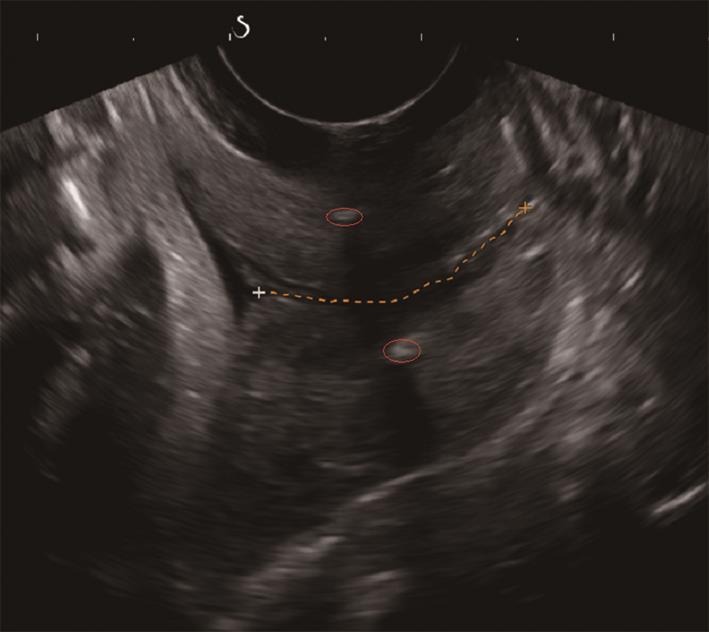

• 剪切波弹性成像测量宫颈硬度的可重复性研究

2023, 48(5):587-590. DOI: 10.13406/j.cnki.cyxb.003223

摘要 (100) HTML (44) PDF 1.18 M (212) 评论 (0) 收藏

摘要:目的 评价剪切波弹性成像(shear wave elastography,SWE)测量育龄期健康未育女性宫颈杨氏模量值的可重复性。方法 由同一名接受过SWE检测培训的高年资医师于同一天不同时间点,前后2次对100名处于育龄期但未育的健康女性宫颈行剪切波弹性成像,测量时选取宫颈4个位点:内口前唇(anterior lip of the inner mouth,IA)、内口后唇(posterior lip of the inner mouth,IP)、外口前唇(anterior lip of the outer mouth,EA)及外口后唇(posterior lip of the outer mouth,EP),获取育龄期健康未育女性宫颈杨氏模量值。使用组内相关系数(interclass correlation coefficient,ICC)评价检查者内可重复性,同时绘制Bland-Altman散点图评价测量一致性。结果 宫颈4个测量位点的前后2次测值均无统计学差异(P>0.05);宫颈IA、EA、EP处杨氏模量值的组内相关系数分别为0.828、0.785、0.768,提示组内可重复性非常好;宫颈IP处杨氏模量值的组内相关系数为0.632,提示组内可重复性好;Bland-Altman散点图提示SWE测量宫颈4个位点杨氏模量值的组内一致性均为好。结论 SWE可用于宫颈硬度的测量,且在宫颈不同位点均具有良好的可重复性与一致性。